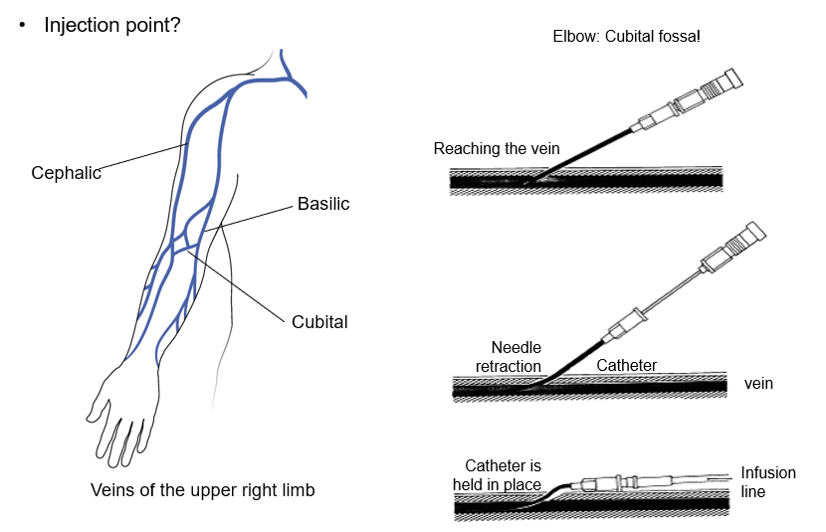

We will talk about venipuncture and injection since many CT studies include the injection of contrast media. It is important to know the signs and symptoms to look for, if there is an allergic reaction of many types, during the contrast injection.

If the patient has an IV in place when they arrive to the CT suite, try to inject the contrast media using a different injection site since the injection will be under pressure rather than slow perfusion. This will help to avoid any local complications at the injection site.

Injection

The injection protocol should be optimized for the scan duration. The protocol will determine when contrast enhancement peaks, how long enhancement lasts, and how it varies over time.

- During the acquisition of images, the patient can be injected with a contrast agent (iodine) to artificially enhance the contrast between tissues

Tingling in the Arm

Prickling or tingling are the two terms used by patients. The contrast comes “under pressure” in the vein. If the tip of the cathlon is close to the wall of the vein it causes stimulation. This feeling is accentuated for patients who have had chemotherapy as their veins have become more sensitive.

Risk of Extravasation

IV infiltration is one of the most common problems that can occur when fluid infuses into the tissues surrounding the venipuncture site. This sometimes happens when the tip of the catheter slips out of the vein, the catheter passes through the wall of the vein, or the blood vessel wall allows part of the fluid to infuse into the surrounding tissue.

Extravasation occurs when there is accidental infiltration of a vesicant that can cause blistering or chemotherapeutic drugs into the surrounding IV site. Vesicants can cause tissue destruction and/or blistering. Irritants can result in pain at the IV site and along the vein and may or may not cause inflammation. Extravasation can result in tissue sloughing, pain, loss of mobility in the extremity and infection.

The extravasation of contrast agents is an unwanted occurrence that can cause irreversible local injuries.

Extravasation of CT scan contrast media into upper extremity subcutaneous tissue is a relatively frequent complication of injection. Contrast extravasation one hour after injection showing a large area in the biceps compartment. Elevation and massage can help with the pain as well as warm compresses.